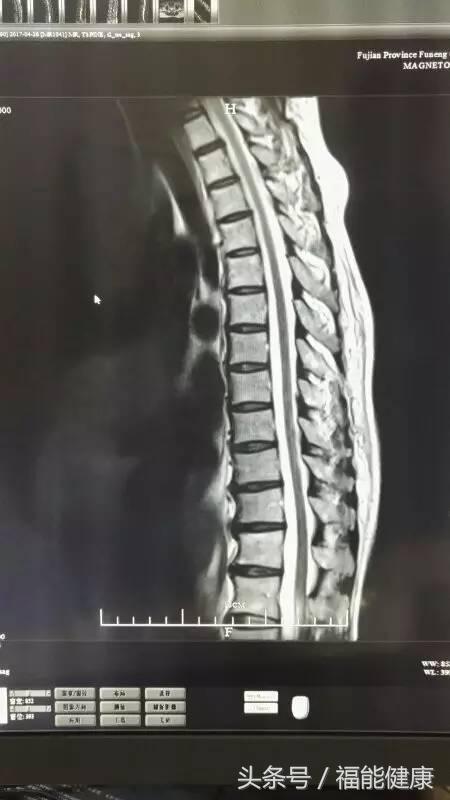

据福能健康管理中心放射影像科主任郑章和介绍,核磁共振对脑、甲状腺、肝、胆、脾、肾、胰、肾上腺、子宫、卵巢、前列腺等实质器官以及心脏和大血管以及骨关节都有很好的诊断功能。核磁共振的原理实际上是,将人体置于特殊的磁场中,用无线电射频脉冲激发人体内氢原子核,引起氢原子核共振,并吸收能量。在停止射频脉冲后,氢原子核按特定频率发出射电信号,并将吸收的能量释放出来,被体外的接受器收录,经电子计算机处理获得图像,这就是核磁共振成像的基本原理。

郑主任谈到,许多人对核磁共振检查的认识是有误区的。实际上,核磁共振是磁场成像,没有放射性,对人体无害,非常安全,这是核磁共振的优势之一。此外,核磁共振在发现病变及发现肿瘤方面也是一把好手,与其他辅助检查手段相比,核磁共振具有成像参数多、扫描速度快、组织分辨率高和图像更清晰等优点。

核磁共振检查不仅可以早期发现某些肿瘤、脑梗塞、脑出血、脑脓肿、脑囊虫症及先天性脑血管畸形,还能确定脑积水的种类及原因等。通过对头部及心脏等部位的核磁检查,在身体健康尚未发出红灯警讯前,早期发现心脏病、脑梗等高风险疾病隐患。当然,MR检查也不是万能的,在很多情况下也需要结合DR、超声、CT等手段,互为补充。同时,在诊断疾病的时候,尚需要密切结合临床其他资料。